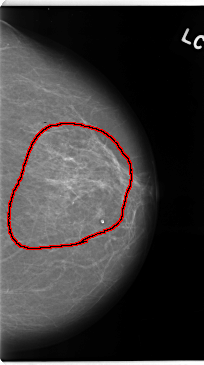

C_0138_1.LEFT_CC

FILE: C_0138_1.LEFT_CC.OVERLAY

TOTAL_ABNORMALITIES 1

ABNORMALITY 1

LESION_TYPE CALCIFICATION TYPE AMORPHOUS DISTRIBUTION REGIONAL

ASSESSMENT 5

SUBTLETY 3

PATHOLOGY MALIGNANT

TOTAL_OUTLINES 1

BOUNDARY